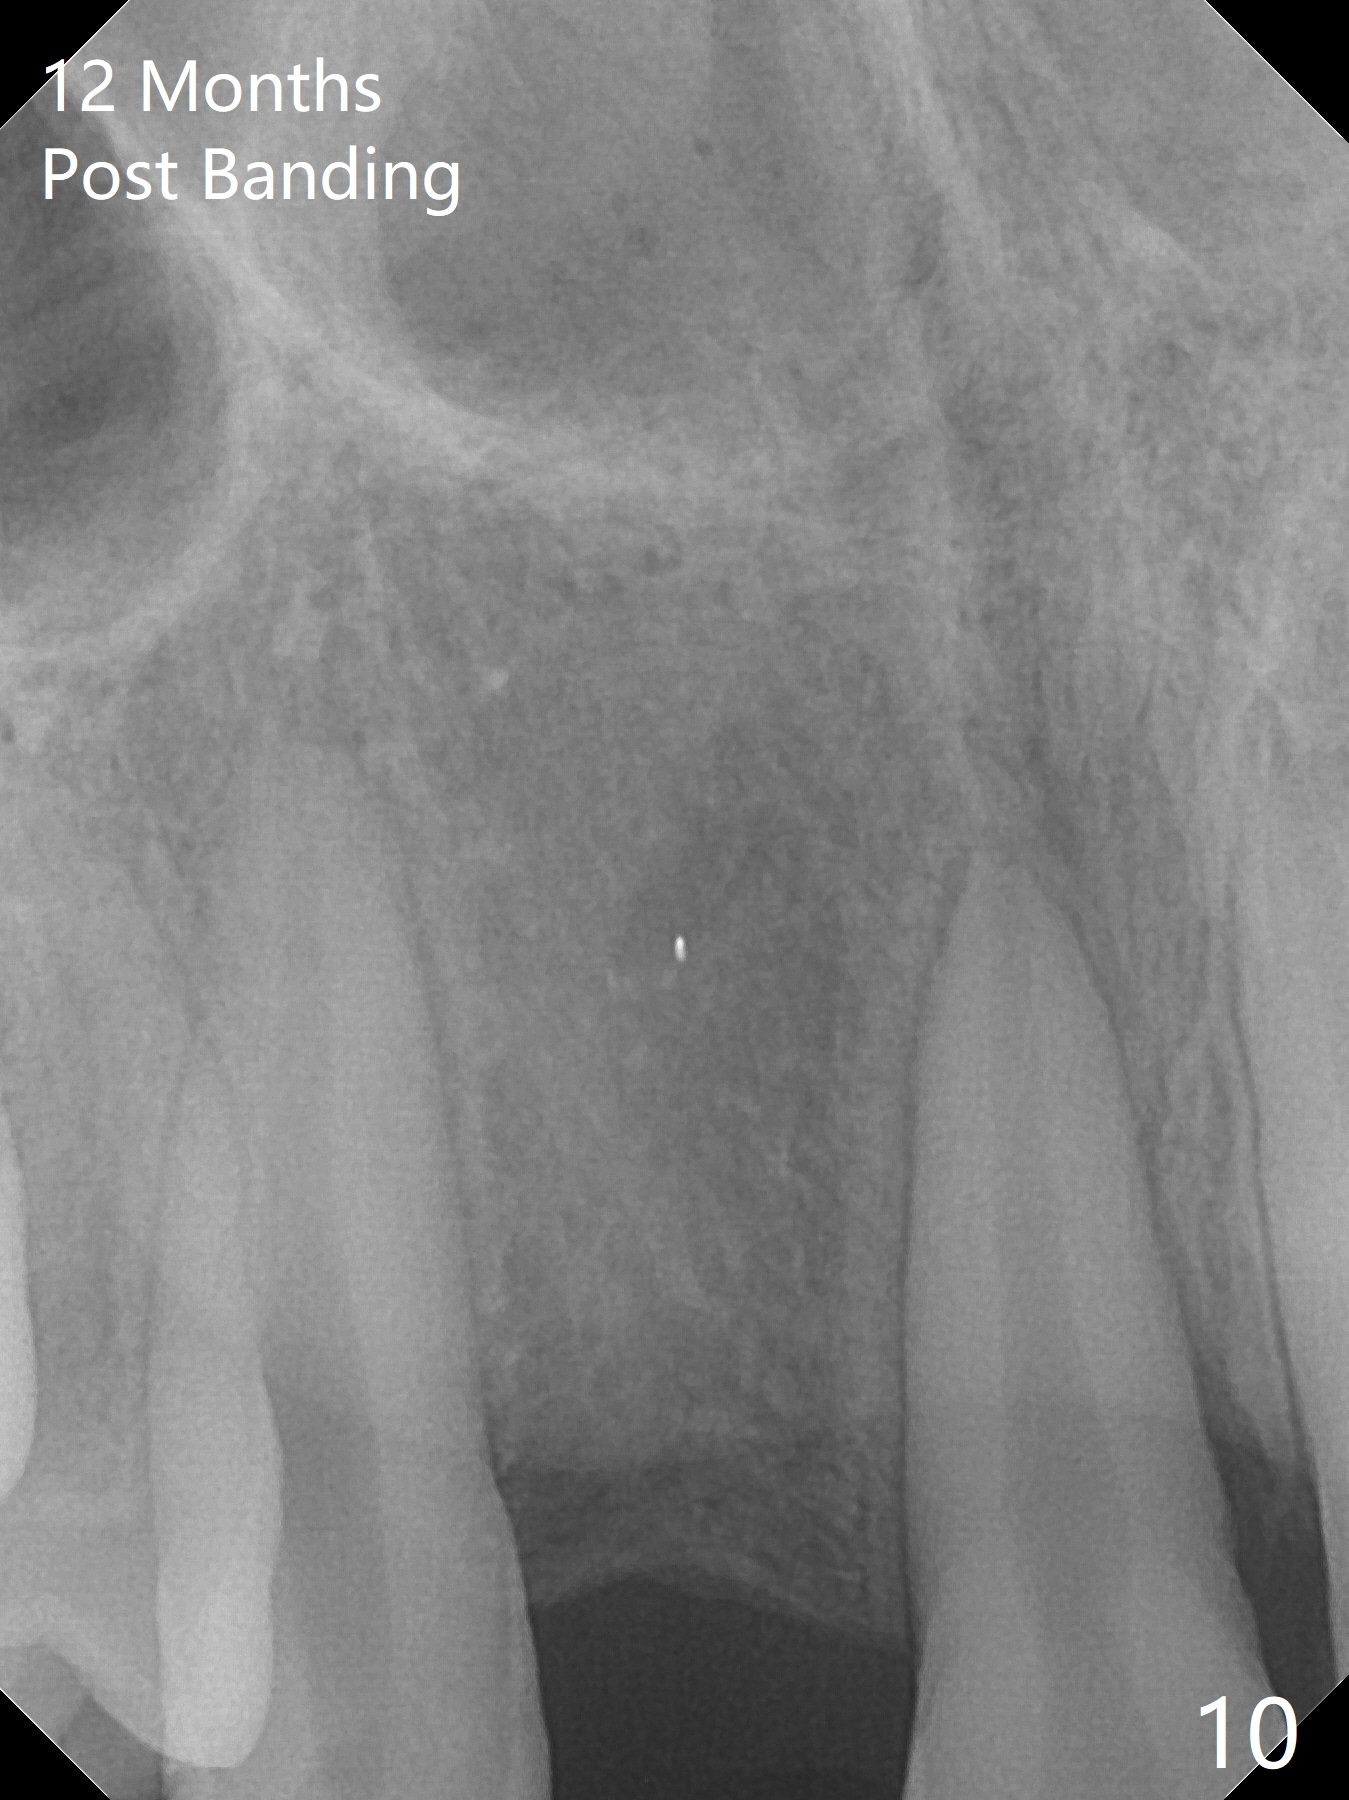

Preop cephalometric tracing shows normal skeletal relationship (Fig.1,2). The upper dental midline deviates to the right (Fig.3). To control root torque, UR1,3 bracketing is intentionally placed off (Fig.4,5, as compared to Fig.6). Take PA for UR1/3 next visit. In fact PA has not been taken. The patient has complained of UR1 turning (mesial incisal edge elongation due to bracket off placement) since the 1st appointment post banding. On the 3rd appointment (2 months 12 days post banding with 18 ss wire), the mesial incisal edge of UR1 and the distal incisal edge of UR3 are trimmed; 18 wires are reused with addition of an open coil spring between UR1-3 (Fig.7). Extra diastemata have appeared mesial and distal to UL1 (Fig.8 *), creating room to correct the upper dental midline shifting. PA is taken 5 months post banding (Fig.9). The roots of neighboring teeth are parallel with new bone formation behind. The mesiodistal space is similar to that of the tooth #10 following consolidation of diastemata on the left. More space is gained 12 months post banding (Fig.10).